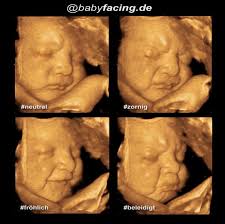

Frauenarzt Gynakologe Dr Med Dorffler Affoltern Am Albis 3d Live 4 D Ultraschall from www.frauenarzt-affoltern.ch Ein unvergessliches, bewegendes erlebnis für werdende mütter und väter ist ein 3d ultraschall bild ihres babys. Allerdings wird er vor allem in der zweiten schwangerschaftshälfte durchgeführt, da zu diesem zeitpunkt die entwicklung des babys. Die wichtigsten fortentwicklungen in dieser zeit erfolgen jedoch im gehirn, da die nervenzellen jetzt in ausreichender. So wird eventuell ein herzfehler, ein offener rücken (spina bifida) oder gesichtsspalten (kiefer, lippen, gaumen) besser entdeckt. Wann ist der ideale zeitpunkt für ein 3d ultraschallbild? Dann findet es womöglich keinen platz mehr. Auch wenn das baby davon nicht mehr als einen leichten druck mitbekommt, solltest. Man weiß noch zu wenig darüber.